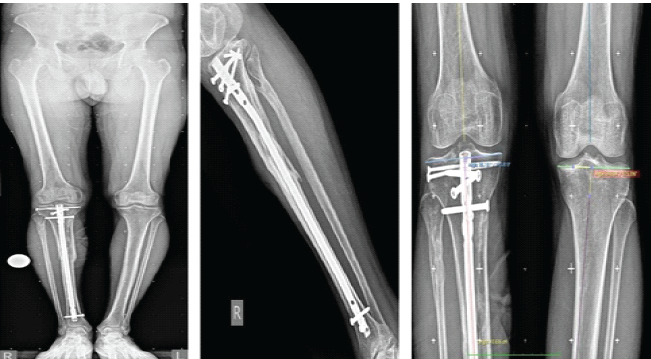

Union (bridging callus across 3 cortices) and alignment on AP, lateral, and long-leg standing radiographs.

A total of 10 patients were included in this prospective case series, of whom 80% were male, and 20% were female, with an average age of 46.9 years (range: 29, 73). The right lower limb was involved in 60% cases on the right side, while 40% patients had fractures on the left side. Based on the Schatzker classification, Type V fractures were observed in 6 patients (60%), while Type VI fractures were present in 4 patients (40%). The mean operative time was 104.3 ± 14.27 min (range: 85–118 min). No intraoperative complications were noted, and there were no cases of non-union, neurovascular injury, revision surgery, or need for plating. All fractures achieved both clinical and radiographic union at a mean of 14.3 ± 1.81 weeks (range: 10–18 weeks) postoperatively. Restoration of the articular surface and tibial alignment was assessed using post-operative anteroposterior and lateral knee radiographs, along with full-length standing views. At the latest follow-up, the mean knee range of motion was 125° ± 7.81° (115, 145) The mean LEFS score was 66.6 ± 7.5, with scores ranging from 53 to 75. The median score was 68, indicating overall good lower limb functional recovery. Most patients (7 out of 10) achieved LEFS scores of ≥64, which corresponds to mild or minimal functional limitation. Only two patients scored below 60, suggesting moderate difficulty in some activities of daily living. All the above results are explained in Table 1. Representative pre-operative, intra-operative, and post-operative images are shown in Fig. 1-5.

Figure 4: Long leg standing view at 12 months shows well-aligned fracture fixation with preserved medial joint space.